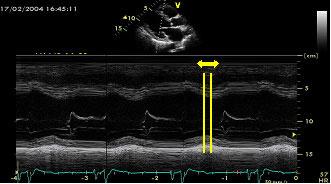

Figure 3

Intraventricular asynchrony determined by M-mode scans in the long axis paraesternal view calculating the time from the septum peak contraction to the posterior wall peak contraction. A delay > 130 ms is diagnostic of LV intraventricular asynchrony.

Among the different echo-measurements, the easiest one to obtain is the septum to posterior wall delay, described by Pitzalis et al using the M-mode (Figure 3). Later, more sophisticated determinations applying Doppler Tissue Imaging derived parameters as described by the group of Bax (Figure 4) and the studies of Yu et al, also demonstrated their usefulness in determining LV intraventricular asynchrony. More recently, some parameters derived from Speckle Tracking Imaging and three-dimensional echo have also shown their usefulness in determining the presence of intraventricular asynchrony, although the degree of complexity in obtaining and interpreting these images increases.